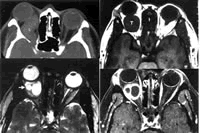

结果发现,接受标准化A/B超检查者37例,CT扫描38例(图1),MRI成像33例(图2)。手术入路选择有外侧开眶(包括改良外侧开眶)26例,内外联合开眶2例,前路开眶4例,内侧开眶2例。其中肿瘤囊内切除21例,肿瘤整体切除15例,部分切除联合术后放射治疗2例。手术并发症包括视力丧失1例,上睑下垂2例,眼球运动障碍2例。(中华眼科杂志 2006,42:585)

图1 右眶神经鞘瘤患者水平CT扫描图像 图像显示右眶内肿瘤呈S形,并蔓延至眶尖(L区)

图2 眼眶神经鞘瘤患者MRI检查结果 图2a为T1WI,显示右眼球突出,球后类圆形占位病变(T区)呈中信号(与眼外肌信号相同)。图2b为T2WI,显示肿瘤周围呈中高信号(细胞成分),中部两个高信号区(液化腔)高于玻璃体信号(箭头)。图2c为Gd-DTPA(二乙烯三胺五乙酸)增强加脂肪抑制扫描结果,显示病变周围增强,中部囊腔不增强, 百拇医药